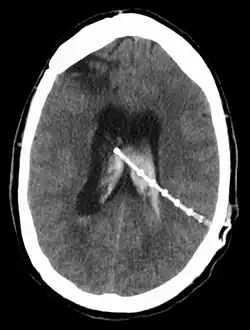

Intraventricular hemorrhage

An intraventricular hemorrhage can occur at any time during or after a shunt insertion or revision. Intraparenchymal hemorrhages that are multi-focal in nature have also been described in the pediatric population following ventriculoperitoneal shunting.[40] The hemorrhage can cause an impairment in shunt function which can lead to severe neurological deficiencies.[36] Studies have shown that intraventricular hemorrhage can occur in nearly 31% of shunt revisions.[41]